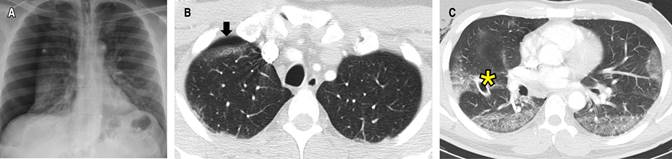

Caso 3. Masculino de 64 años, sin antecedentes relevantes ni tabaquismo. Ingreso hospitalario al día 11 de inicio de síntomas dados por disnea asociada a desaturación a medio ambiente (SaO2 85%), con confirmación molecular de infección por SARS-CoV-2 y radiografía de tórax con OVE difusas. El tratamiento inicial consistió en oxígeno (FiO2 32%), antipiréticos y dexametasona IV según el ensayo RECOVERY.20 Al día cuarto de estancia (día 15 de síntomas) presentó tos persistente, mayor deterioro del patrón respiratorio e hipoxemia severa sin mejoría con máscara de no reinhalación (FiO2 90%), ni pronación, además presencia de crepitaciones cervicales izquierdas. Paraclínicos con leucocitosis (16,600 cel/μL), linfopenia (300 cel/cel/μL), elevación de la LDH (524 U/L), hiperferritinemia (4,519 ng/mL) y DD en 630 ng/mL. Requirió intubación orotraqueal y traslado a la UCI. Se consideró descartar complicaciones de la COVID-19, se realizó una angio-TC de tórax que mostró TEP agudo y neumomediastino con enfisema cervical izquierdo (Figura 4). Se indicó anticoagulación con heparina de bajo peso molecular (1 mg por kg cada 12 horas), antibióticos y VM. Se realizaron otros estudios como fibrobroncoscopia y endoscopia de vías digestivas altas sin evidenciar hallazgos anormales. Se consideró neumomediastino espontáneo asociado a neumonía severa por SARS-CoV-2. Cirugía de tórax optó por manejo conservador, con una evolución hacia la mejoría y egreso al día 40. A los tres meses se realizaron pruebas de función pulmonar con espirometría sugestiva de restricción y capacidad de monóxido de carbono (DLCO), moderadamente disminuida (Tabla 1). En la actualidad continúa en sesiones de rehabilitación pulmonar con mejoría de la disnea.

Figura 4: Angio-TC, ventana para pulmón corte axial (A) y coronal (B). Se observan opacidades en vidrio esmerilado, neumomediastino (flechas) y enfisema de los tejidos blandos de la región cervicotorácica izquierda (asterisco).